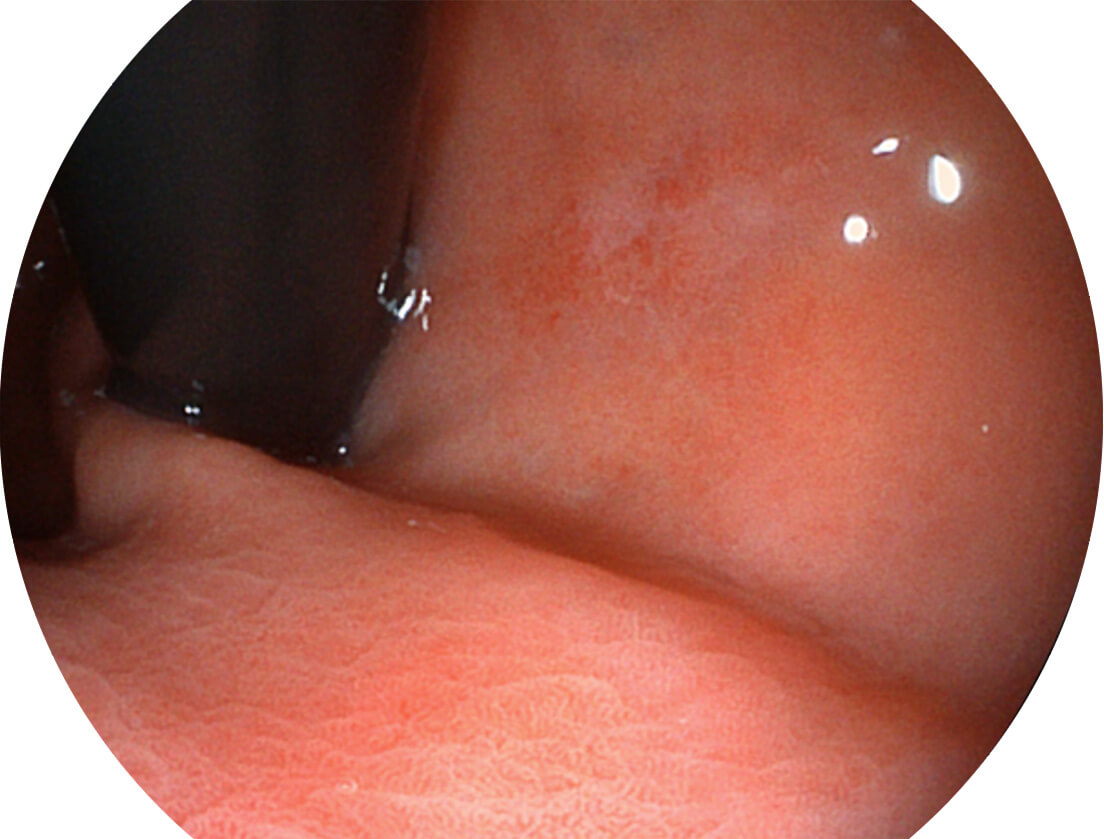

SFI图像

图像具有高亮度、高黏膜血管颜色对比度的特点,且不改变粘液、食物残渣、粪便的基本颜色,可在中远景下进行观察,助力消化道早期疾病的诊断。